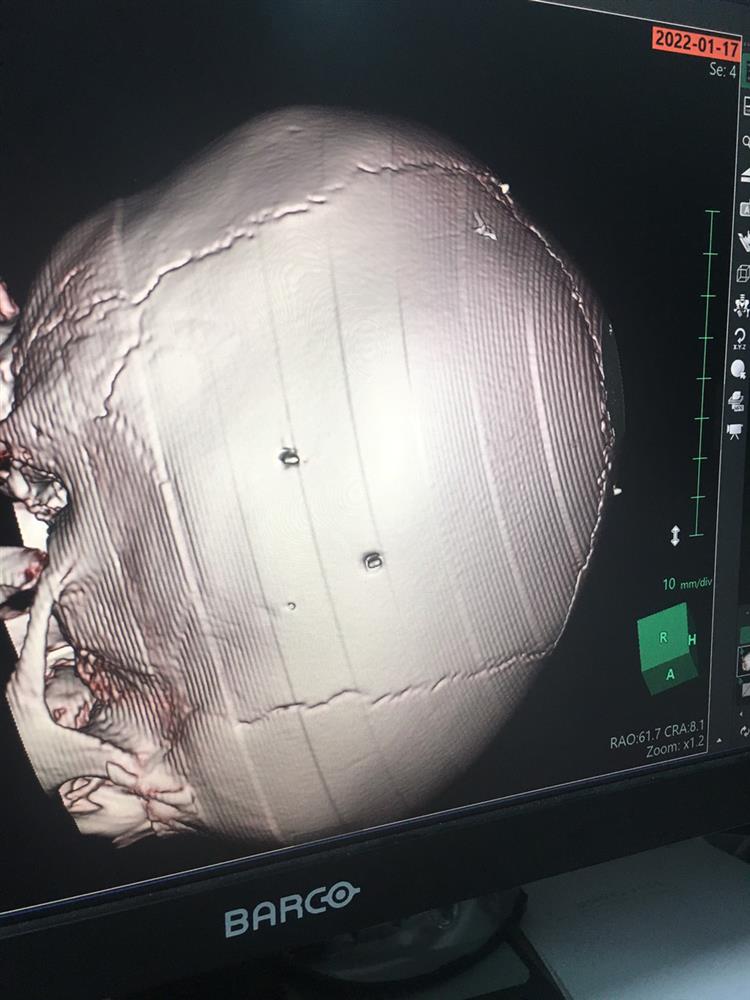

Hình ảnh phim chụp đinh trong đầu bệnh nhi.

Lỗ đinh trên hộp sọ bệnh nhi.

Đáng chú ý, tại Bệnh viện Đa khoa Xanh Pôn, kết quả phim chụp cắt lớp cho thấy bệnh nhi Đ.N.A có hình ảnh như bị đinh bắn vào sọ. "Có 9 chiếc đinh. Bệnh nhân đang trong tình trạng rất nặng, đe dọa tử vong cao", BS Kiên cho biết thêm.